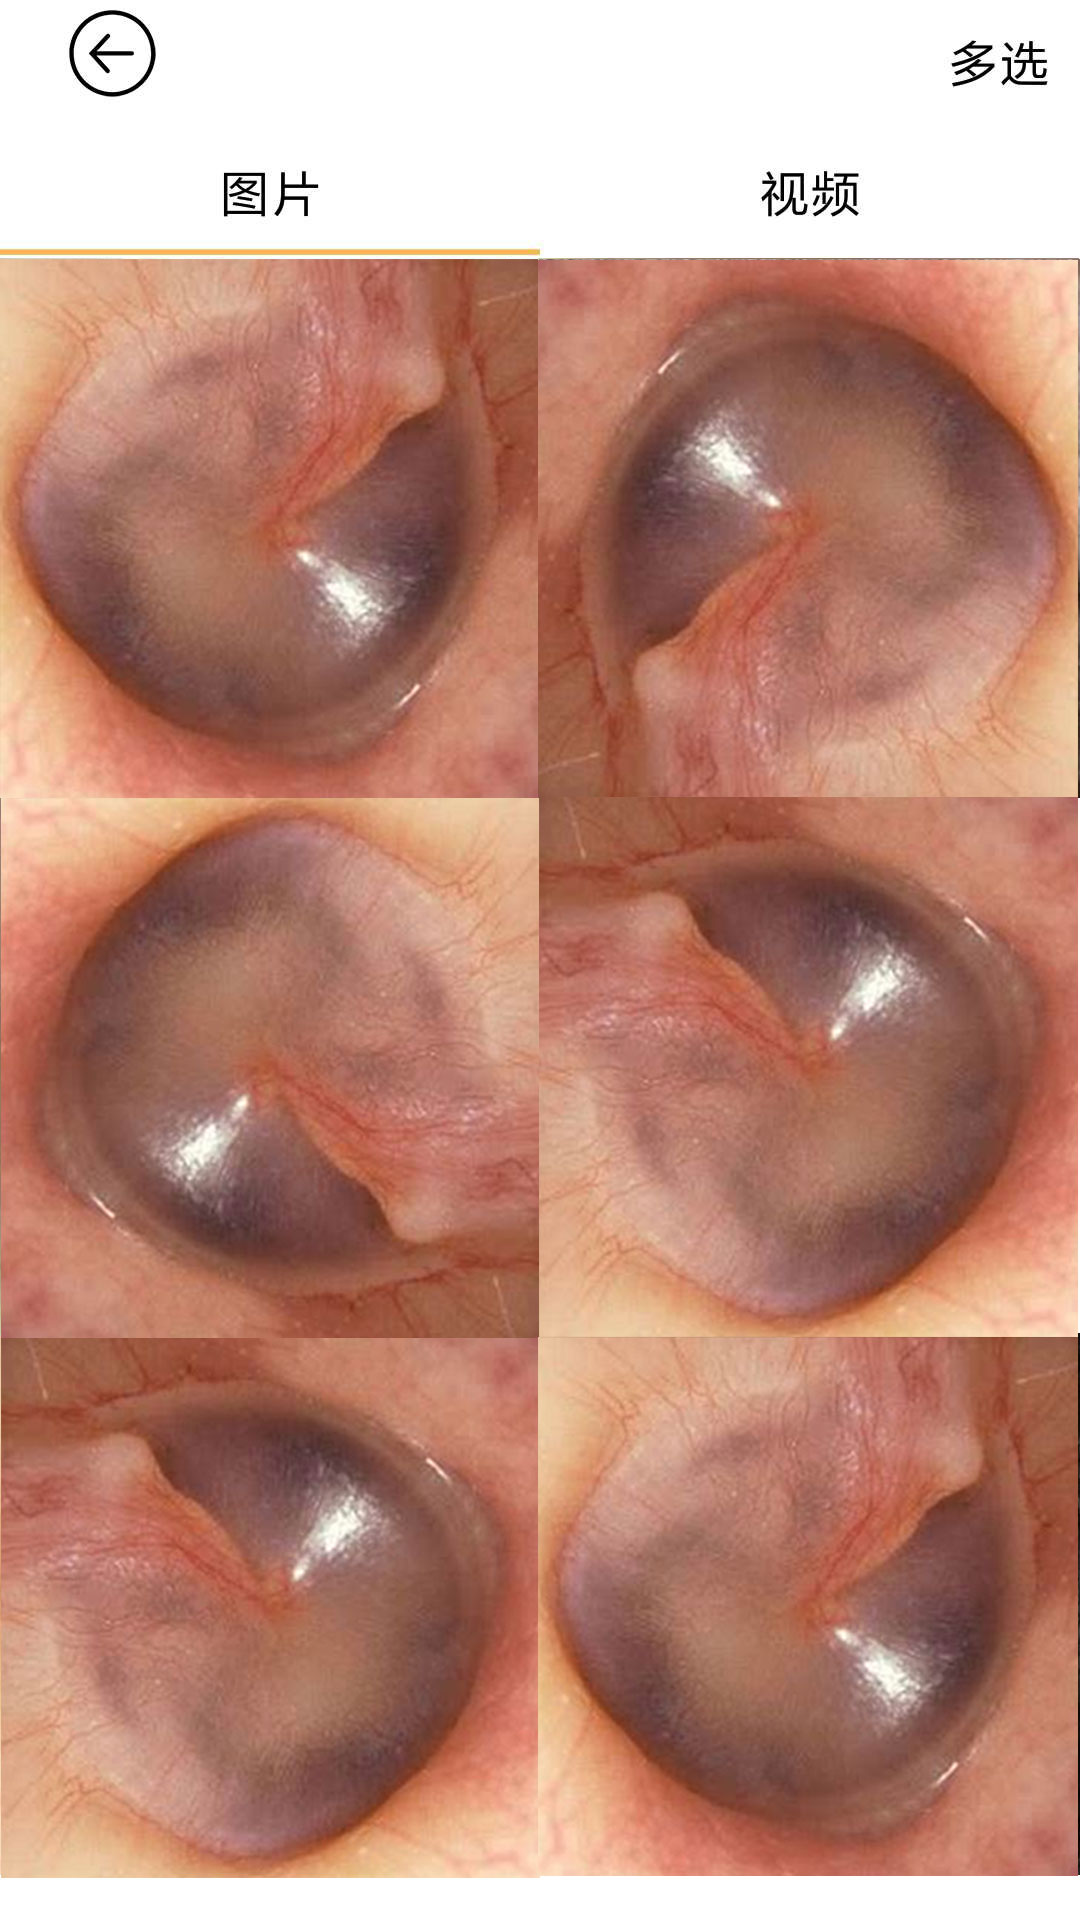

“bebird是一款專業(yè)個人健康護理類App�����,通過wifi與bebird可視采耳儀連接����,可以在App顯示清理耳道的實時畫面,個人可以輕松安全的享受采耳過程���。

采耳過程可拍照、錄像��,為防止采耳過程誤觸屏幕還設有采耳過程鎖屏功能���;